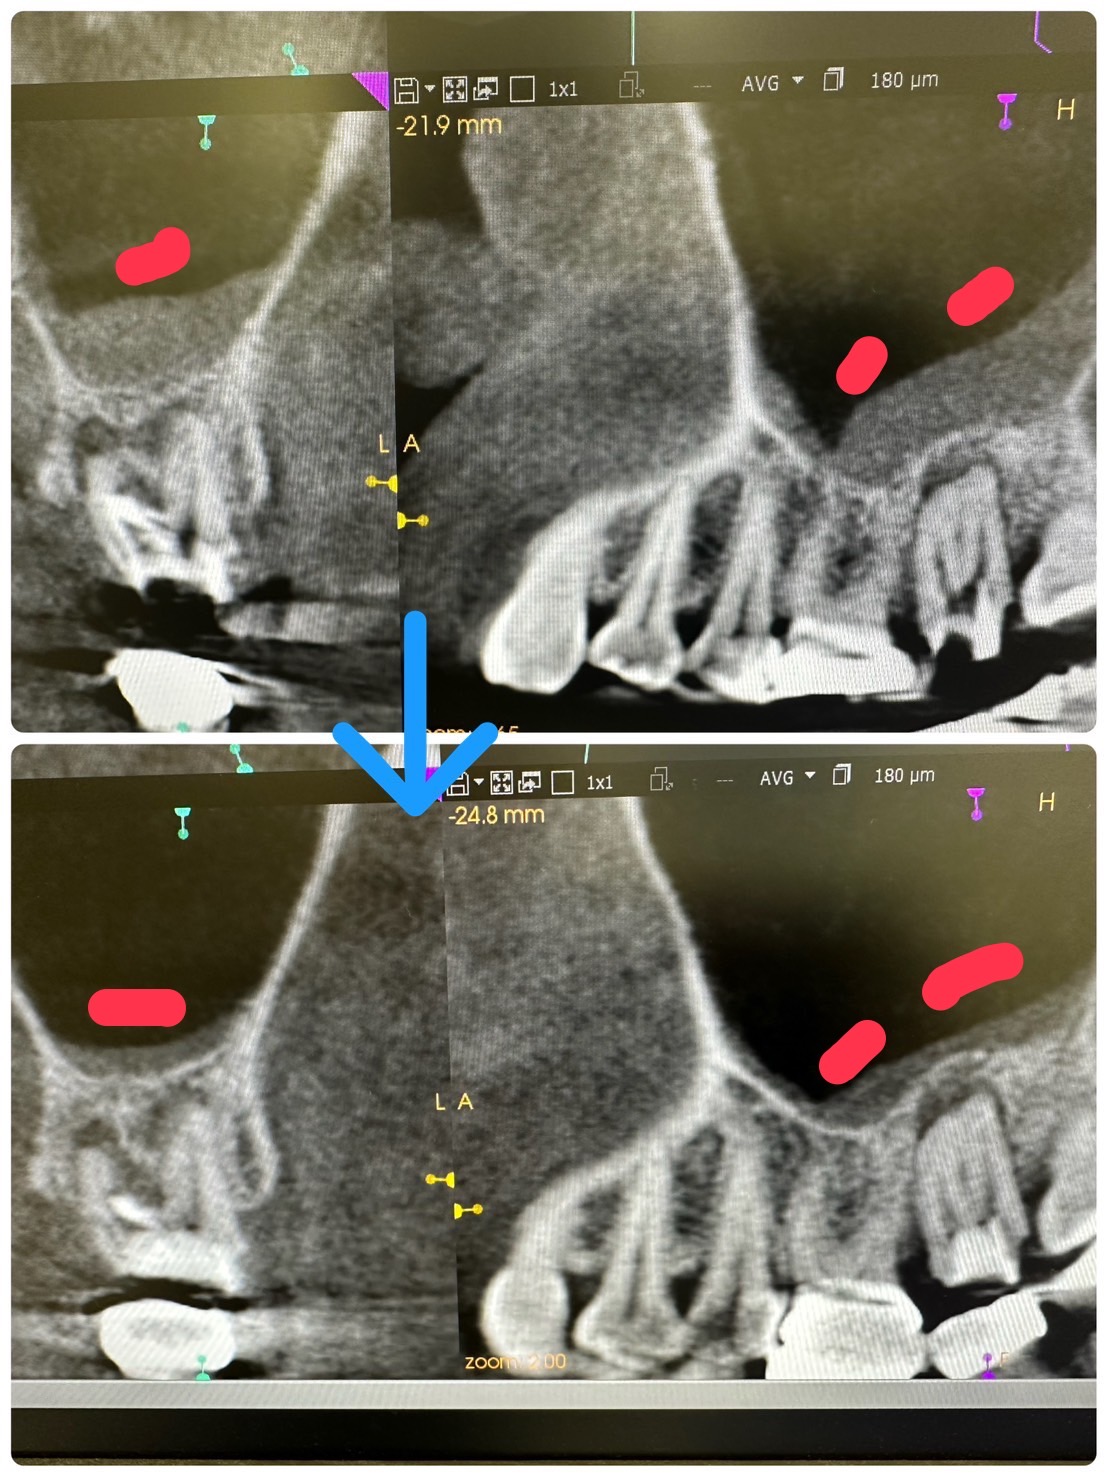

歯性上顎洞炎、順調に回復傾向